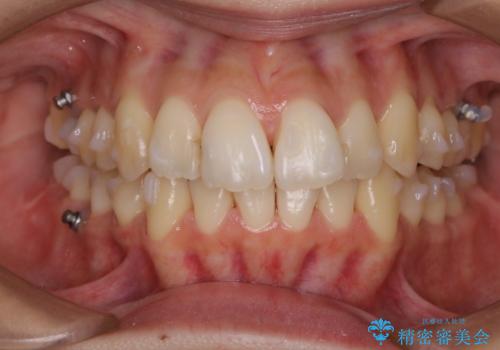

インビザラインの経過と一緒にクリーニング(PMTC)

矯正スタート前に全体のクリーニング(PMTC)

インビザライン中のクリーニング(PMTC)

インビザラインの矯正チェック時にクリーニングも